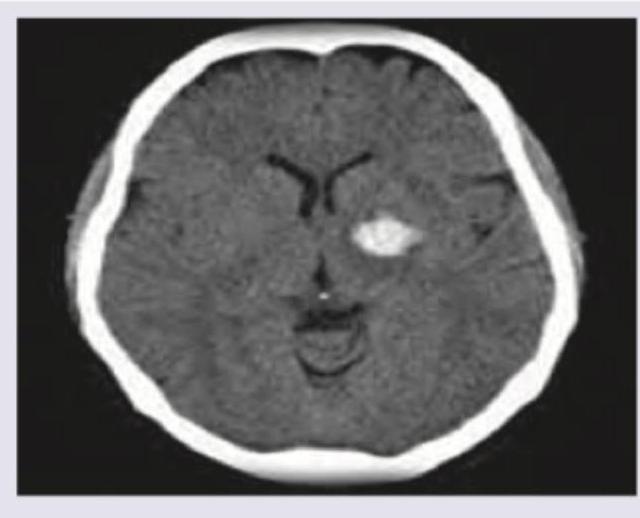

A 70-year-old Caucasian male presents to the emergency room following a fall. The patient's past medical history is significant for myocardial infarction and atrial fibrillation. His home medications are unknown. The patient's head CT is shown in Image A. Laboratory results reveal an International Normalized Ratio (INR) of 6. Which of the following is the most appropriate pharmacologic therapy for this patient?